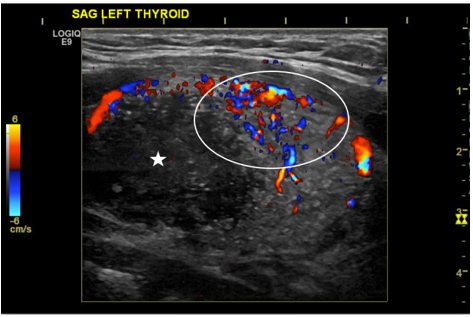

Papillary thyroid cancer has the fastest increasing incidence of any thyroid malignancy and accounts for the majority of thyroid neoplasms (75-85%). It is also the most common type of thyroid cancer to develop from radiation exposure1. Papillary thyroid cancer typically occurs in caucasions and has a female predilection (3:1 ratio), with a peak age of incidence between 25-50 years-old. It commonly presents as a painless neck mass. While no specific laboratory tests exist for diagnosis, elevation in thyroxine, triiodothyronine, or TSH can be seen. Radiology plays a crucial role in the diagnosis of papillary thyroid cancer, with ultrasound being one of the initial steps in the workup. Radioiodine (I-131) nuclear medicine studies can be used to check for distant metastases and ablate thyroid cancer. Thyroid lobectomy is the main treatment, with total thyroidectomy being reserved for higher risk tumors. We report an unusual clinical presentation of the diffuse sclerosing variant of papillary thyroid cancer in a 16-year-old male, who presented with a painless neck mass that had been growing over the past year. The patient subsequently received a total thyroidectomy and radioiodine treatment.References